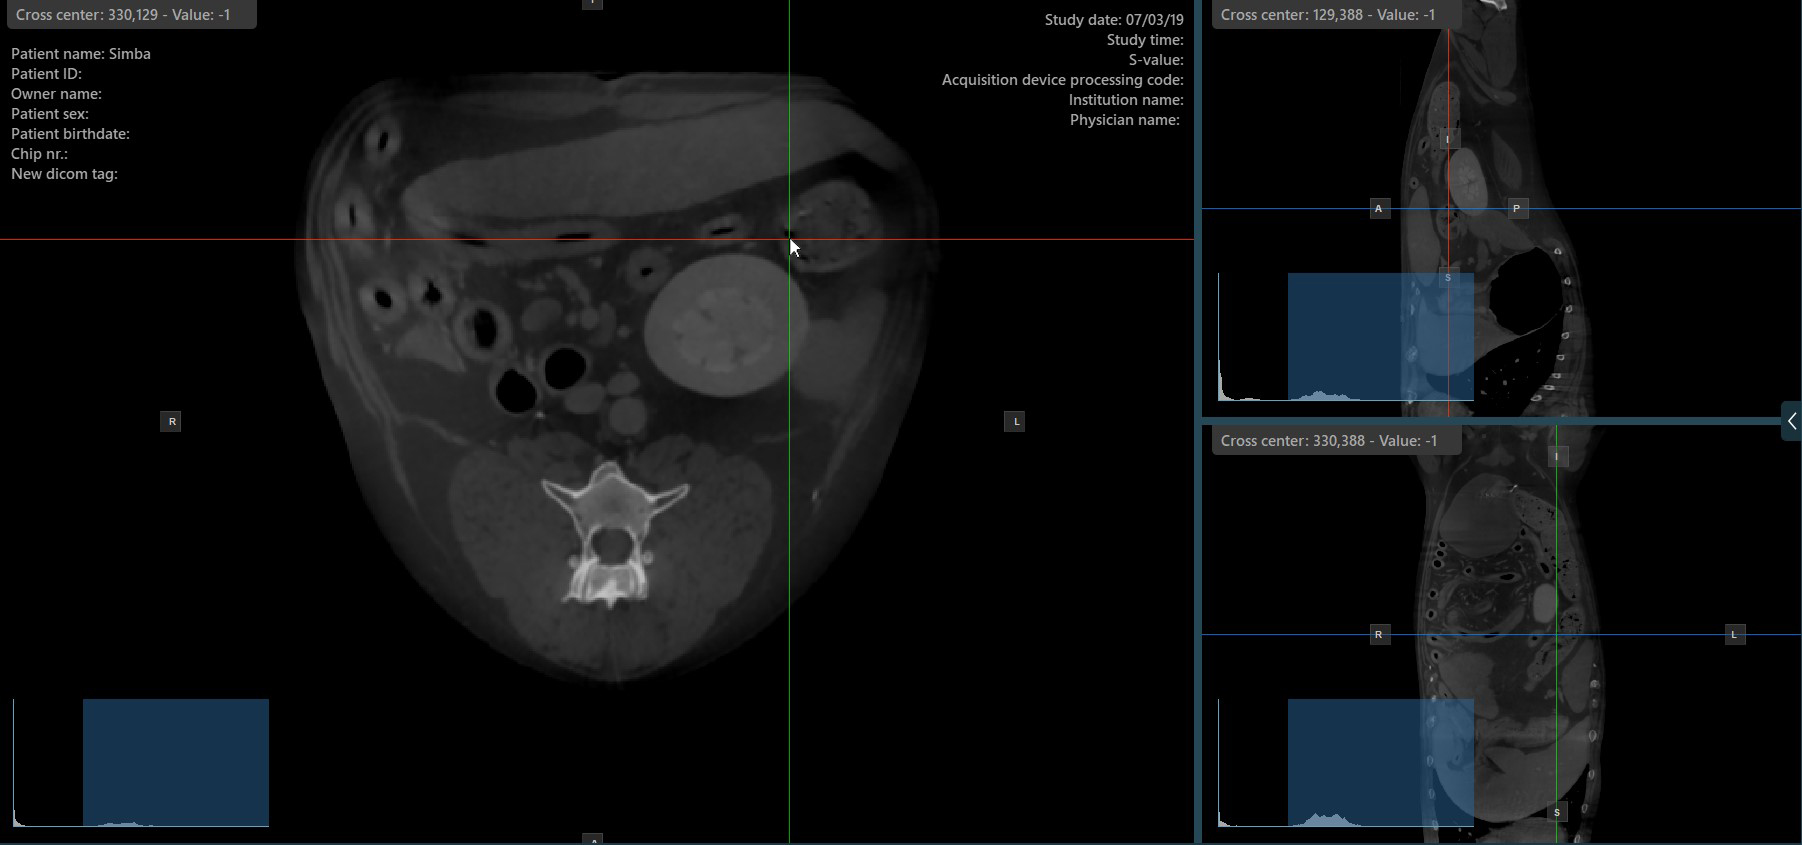

Change Slicers Cross Center Position¶

Altering the position of the cross center of slicers will change the position of the corresponding two image planes. The cross center of the slicers can be selected by using the Select Item (Default)

tool, assigned to the right mouse

button by default.

Once selected, drag the cross center of the specific slicers to the desired direction to move its position. The corresponding image planes’ orientation changes accordingly.